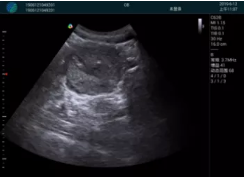

清晰顯示腺體內(nèi)低回聲快影,邊界清晰,包膜較光滑

腺體內(nèi)部清晰顯示一低回聲塊影,形態(tài)不規(guī)則,邊界模糊,邊緣呈毛刺狀,內(nèi)部見砂礫樣鈣化

M20查看:囊內(nèi)回聲均勻,邊界清晰,囊壁光滑